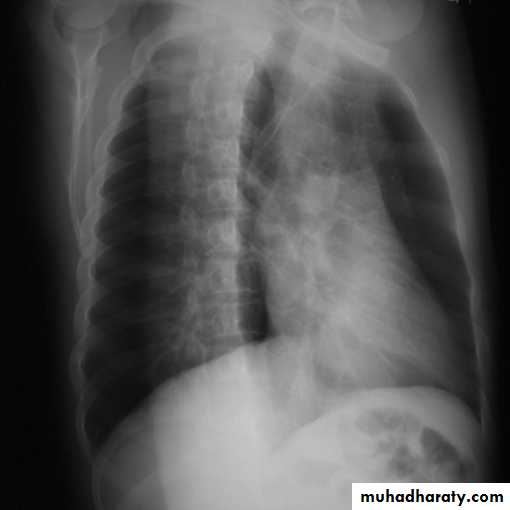

Bronchectasis

Abnormal irreversible dilatation of bronchioles with thickening of their walls . Presented with recurrent pneumonias & haemoptysis ..Types:Cystic

Fusiform

Cylendrical

In which the bronchiole is wider than the near by vascular branch

Causes –infancy & childhood infection

-TB

-pulmonary fibrosis

-cystic fibrosis

-immotile cilia syndromes